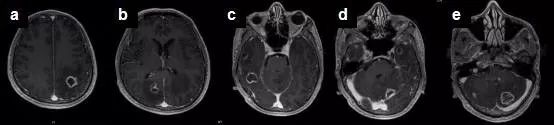

她不敢耽搁,到医院就诊,做了头部MRI(见下图)和肺部CT,提示:颅内多发占位:转移瘤?、右侧肺炎。

钟爱的头部MRI虽然报告转移瘤可能,但临床和病程演变更像是感染性疾病,结合其弓形虫抗体IgM、IgG均为阳性,故高度怀疑弓形虫脑病,即可启动了磺胺类药物的治疗,2周后复查头部MRI,提示大部分病灶已消失,小脑和左侧顶叶的病灶也明显缩小。

弓形体脑病是AIDS患者最常见的脑内占位性病变,随着抗逆转录病毒治疗的普及,该病的发病率在逐渐降落。弓形虫是专性细胞内寄生虫,主要包括卵囊、组织囊和速殖子等三种形态,猫科动物为其最终宿主,由粪便排出后卵囊后,由进食受感染的猪肉、羊肉等传染给人,在肠道中释放出速殖子,通过血流播散,并在有核细胞内增殖,存活的虫体主要藏身于脑、心肌、肺、骨骼肌和视网膜中,一般处于休眠态势直至宿主死亡。据报道全世界约有1/3的人群存在弓形虫慢性感染,随着AIDS患者细胞免疫的不断衰退,尤其当CD4+T淋巴细胞数低于100/ml时,弓形虫潜伏感染被激活,转而攻击宿主,导致弓形虫脑病的发生,额叶和顶叶是最常受累的脑区,尤其是皮髓交界区和基底节区,颞叶、枕叶、小脑或丘脑亦可受累。头痛和发热是TE最常见的临床表现,发生率高达90%,意识模糊、嗜睡亦很常见,也有以癫痫为首发症状者。

弓形虫脑病患者大多数血清抗弓形体抗体阳性,通过留取脑脊液标本行PCR检测弓形体基因组中一条529bp的特征性片段,其诊断灵敏度为68.8%,特异性高达100%。弓形虫脑病在影像学上特征性地表现为多发环状强化病灶,周围伴有水肿和占位效应,MRI检查较CT更为敏感。多数情况下,依据CD4+T淋巴细胞数,血清学检查,临床表现,以及特征性的影像学表现,即可拟诊TE并启动治疗,如果经验性治疗有效,便可确定诊断,仅仅在上述证据不够而导致诊断困难时才考虑开颅活检。